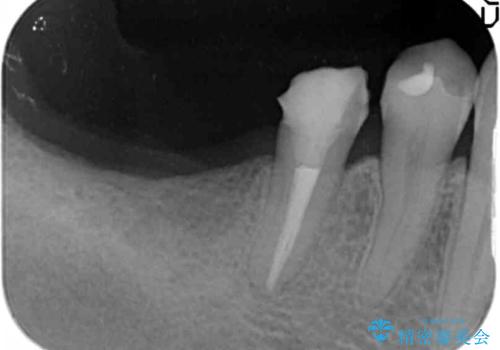

インプラント治療による咬合機能回復

- 失ってしまった奥歯の咬合機能の回復を求めて来院されました。

骨の幅が十分にないのでインプラント治療に伴い、人工骨の造成を同時に計画します。

インプラントは高い確率で骨に結合し、しっかりとした咬合力を回復することができます。

長年安心してしっかりと噛んでいただけるよう今回は骨を増成する治療計画としました。